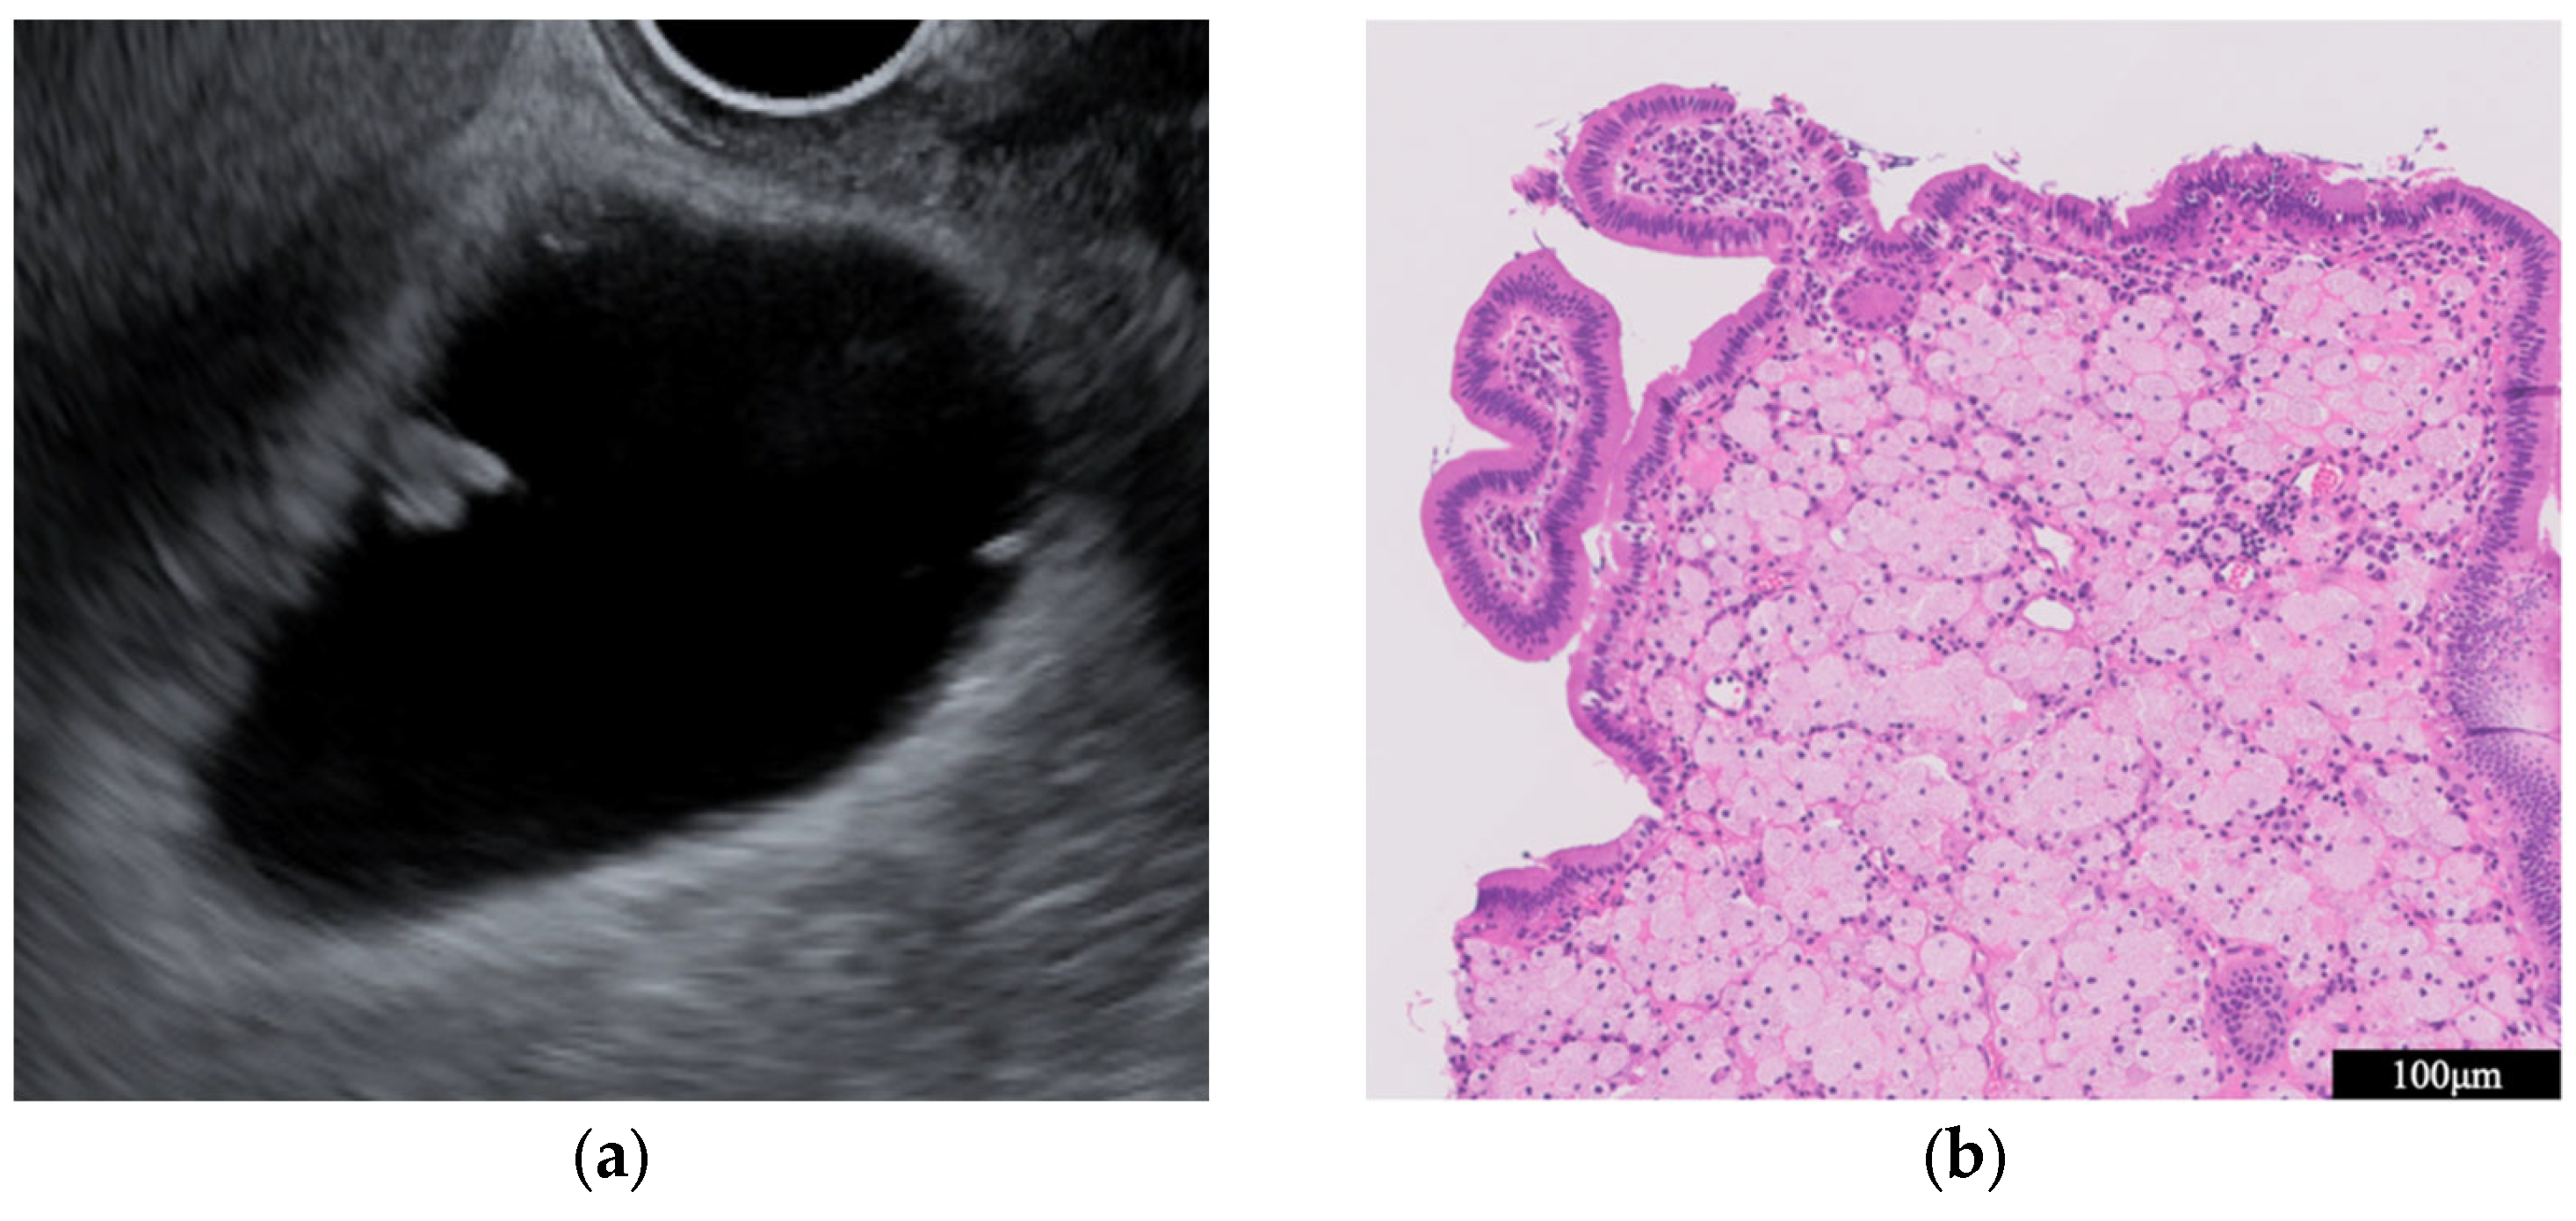

- GB mucosal hyperplasia associated with pancreaticobiliary maljunction (PBM) (Figure 4)

| GB mucosal hyperplasia associated with pancreaticobiliary maljunction | Smooth | Uniform hypoechogenicity | Preserved |